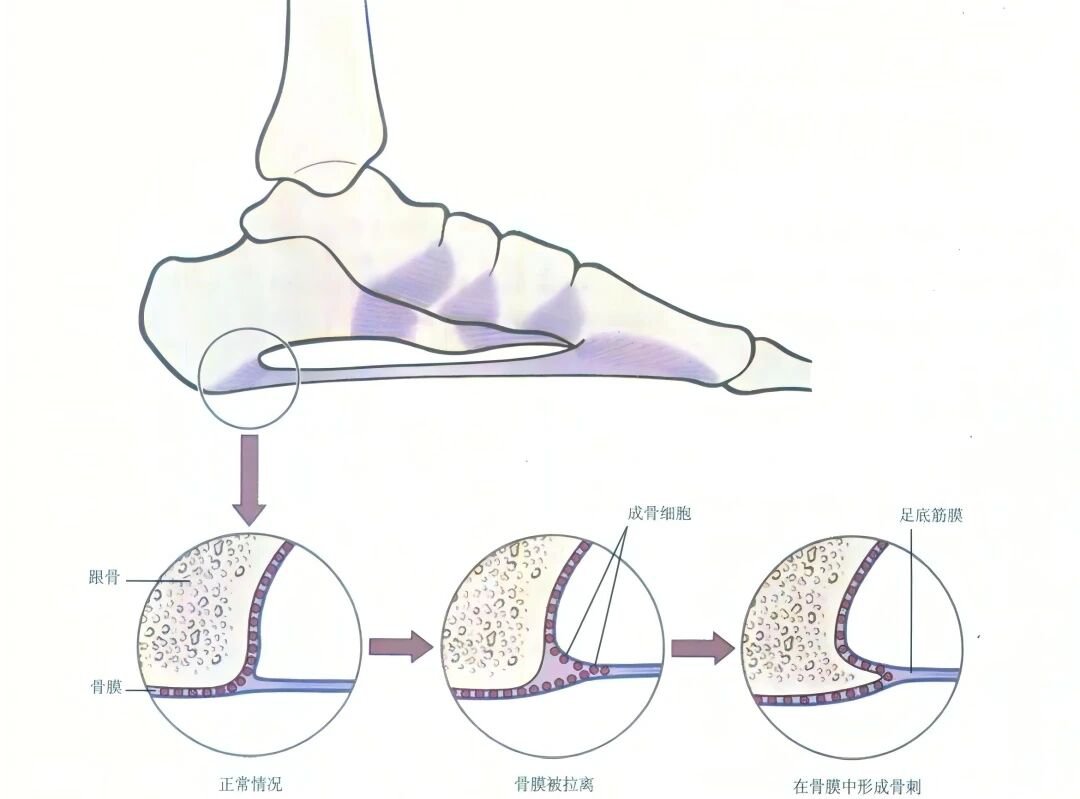

3、足跟骨质增生

即“足跟骨刺”,当足跟关节出现磨损、破坏后,人体会进行自我修复、硬化与增生,从而形成足跟骨刺,是一种自然的老化现象。

示意图片来源于网络,侵删